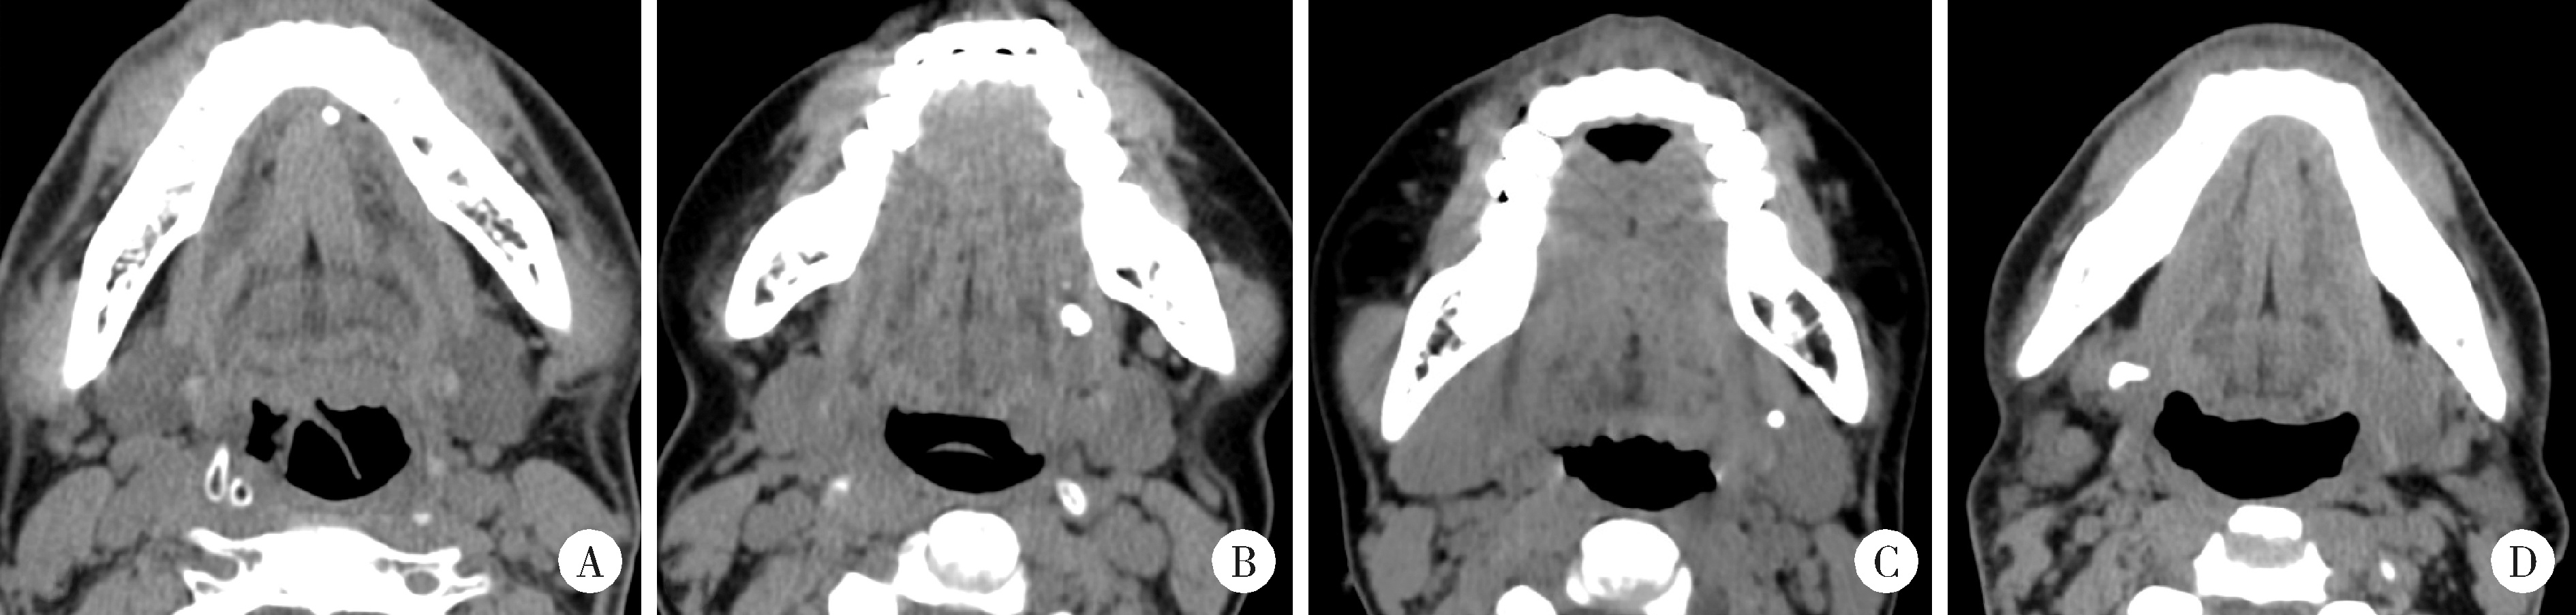

Figure 2

Axial images of spiral CT showing the calculi of the submandibular gland A, calculus in the anterior segment of the left submandibular gland duct; B, calculus in the middle segment of the left submandibular gland duct; C, calculus at the hilum region of the left submandibular gland; D, intraglandular calculus of the right submandibular gland."